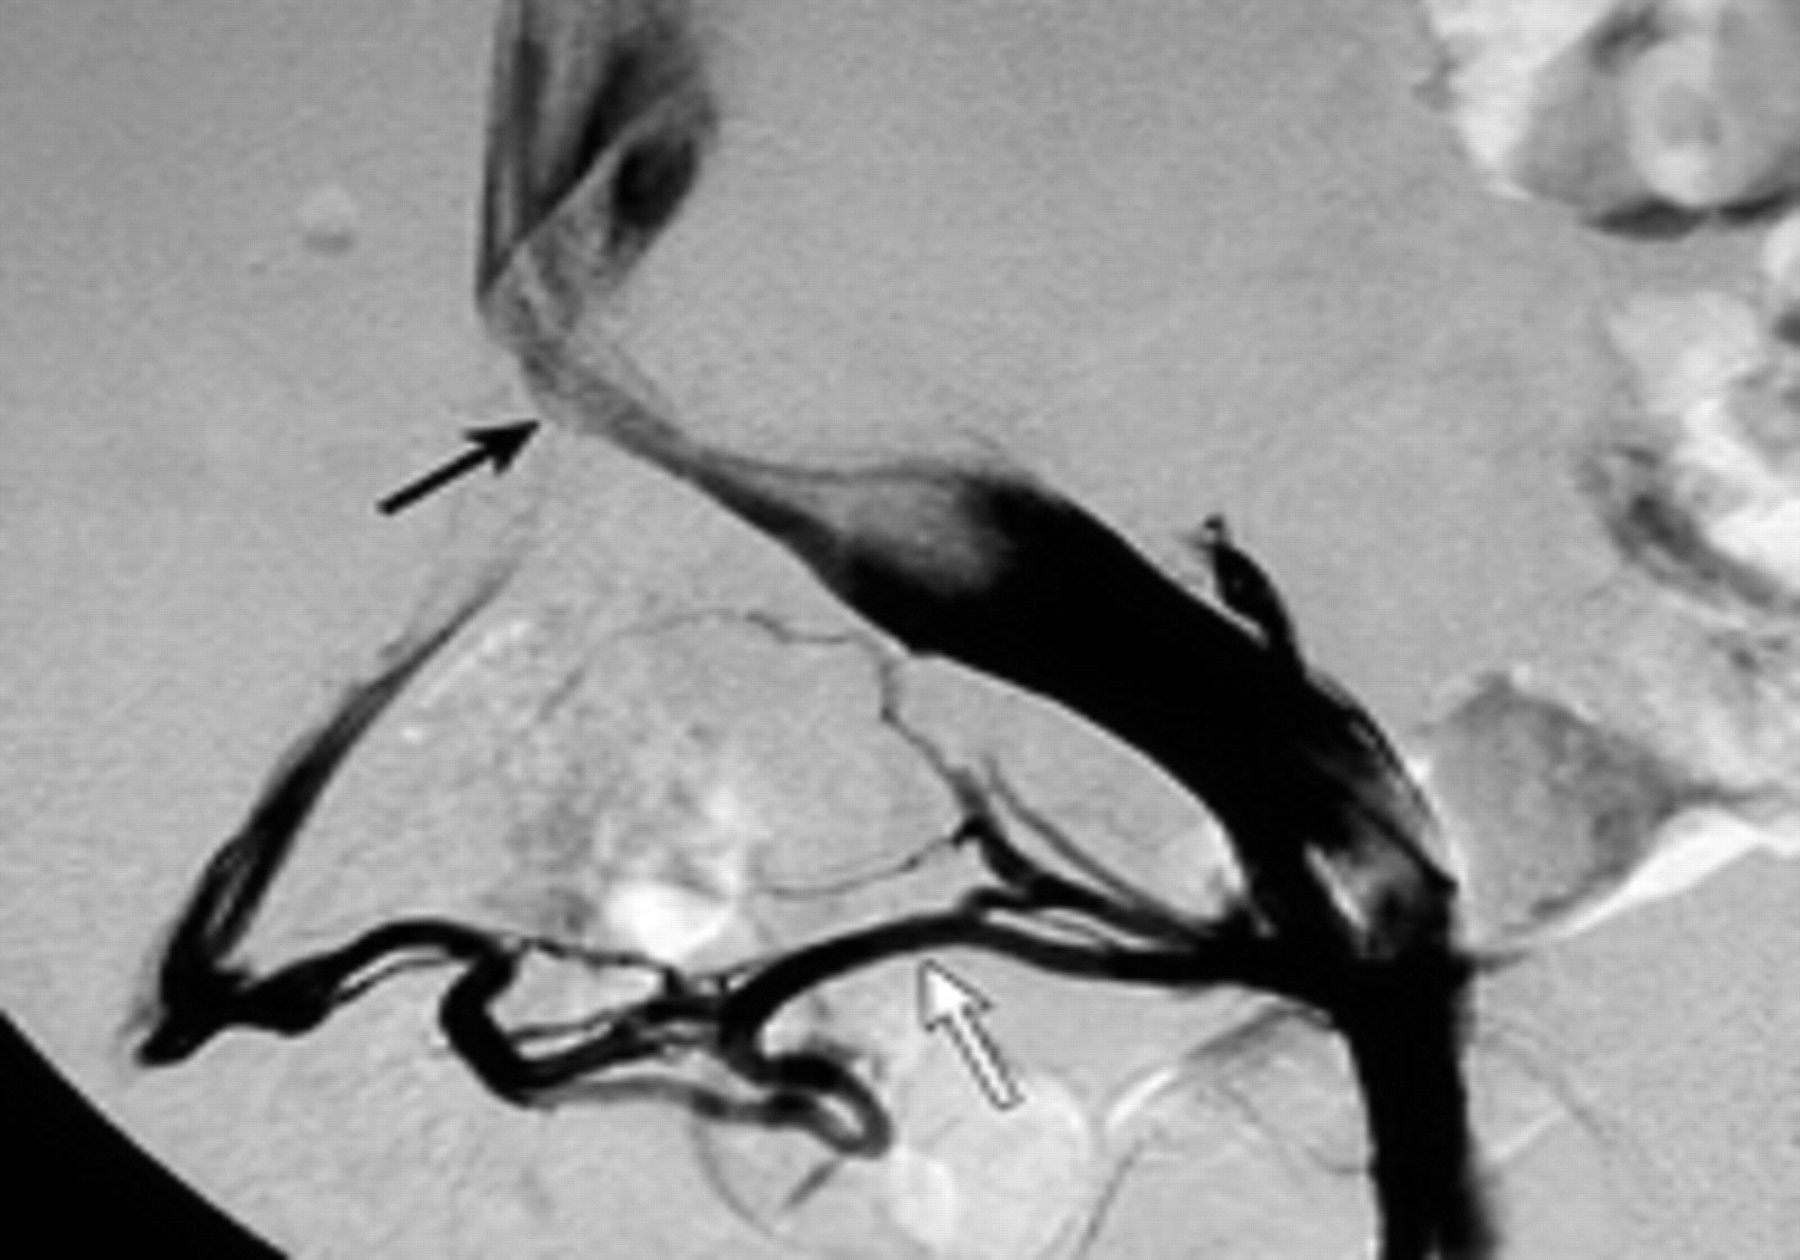

یکی از راههای تشخیصی خوب برای این سندروم استفاده از آنژیوگرافی است. در آنژیوگرافی که در کت لب انجام میشود با استفاده ماده حاجب و گرفتن تصاویر مناسب می توان انسداد و شدت آن را بررسی کرد و در ادامه آن را درمان کرد.